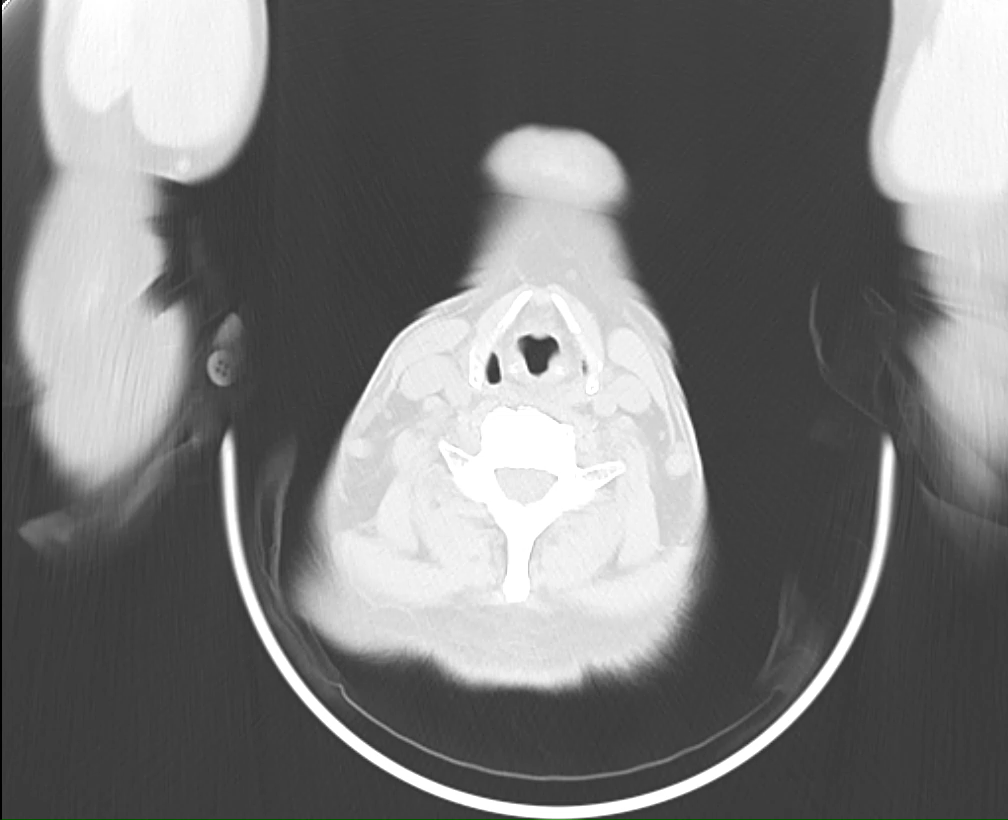

2025-09-14CT胸部平扫:1、右肺上叶肺门结构不清伴纵隔淋巴结增多,请结合临床病史及纤支镜检查、随诊;2. 右肺上叶条索、结节灶(伴部分钙化),考虑纤维增殖性病变?,随诊;3. 两肺小结节及钙化灶,两肺散在少许炎性改变, 请结合临床、随诊。

电子支气管镜:局麻满意后经鼻进镜,气管:气管通畅,隆突锐利,粘膜光滑。

右侧:右主支气管、右中间段、右中叶、右下叶及各级支气管管腔通畅,粘膜光滑,未见新生物;右肺上叶开口狭窄,表面粘膜充血水肿,疑似外压,未见明显新生物,在此处予以刷检、灌洗,送细菌学、细胞学及tNGS检查。

左侧:左主支气管、左下叶支气管及各级支气管管腔通畅,粘膜光滑,未见新生物;左上叶开口粘膜表面稍充血伴水肿,开口狭窄。术毕,术中无活动性出血,患者安返病房